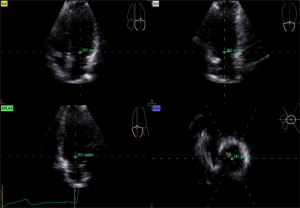

Image acquisition and data analysis of RT-3D Auto LAQ

RT-3D Auto LAQ image acquisition operation guidelines: (I) use the 4Vc matrix probe was to obtain two-dimensional images at the standard four-chamber heart section, and adjust the sector depth and gain to make the left atrium clearly visible in all the apex views; (II) Breath-hold at end-expiration; acquire 4–6 cardiac-cycle four-dimensional (4D) full-volume loops; (III) transfer to EchoPAC; select the best loop, open 4D Auto LAQ; (IV) at end-systole, place the sampling point at the mid-mitral annulus in each apical plane; align axes; (V) activate the “review” interface to check whether the LA endocardium curve automatically outlined by the system is consistent with the real endocardium. If there is any deviation, manually drag and drop the sampling line to make it coincide with the endocardium while excluding the pulmonary vein inlet and LA auricle area, then click “result” for LA volumes and strain, as shown in Figures 1-4. The LA volume parameters are divided by the body surface area (BSA) of each case to obtain the corresponding volume indices. Further calculations are performed to determine the left atrial total emptying fraction (LATEF) = (LAVmax-LAVmin)/LAVmax; left atrial passive emptying fraction (LAPEF) = (LAVmax-LAVpreA)/LAVmax; left atrial active emptying fraction (LAAEF) = (LAVpreA-LAVmin)/LAVpreA; and left atrial expansion index (LAEI) = (LAVmax-LAVmin)/LAVmin. The LA function parameters include the left atrial storage period strain (LASr), the left atrial conduit period strain (LAScd), the left atrial systolic period strain (LASct), and the corresponding left atrial storage period circumferential strain (LASr-c), left atrial ductile period circumferential strain (LAScd-c), and left atrial systolic period circumferential strain (LASct-c) (16). Among them, LAEI, LASr, and LASr-c represent the storage function of the left atrium; LAPEF, LAScd, and LAScd-c represent the function of the LA duct; and LAAEF, LASct, and LASct-c represent the active contraction pump function of the left atrium. All parameters were averaged twice.